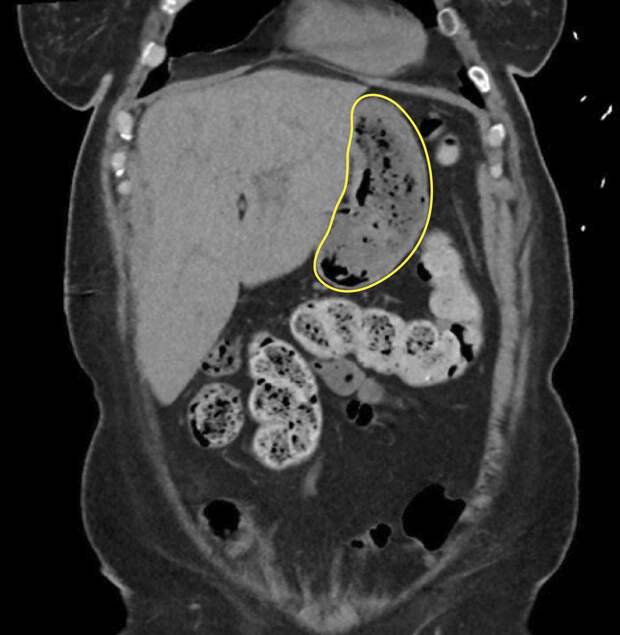

Сканирование с помощью неинвазивного метода МРХПГ (магнитно-резонансная холангиопанкреатография) выявило в желудке образование, похожее на скопление воздуха. А во время эндоскопии врачи обнаружили безоар — комок инородных тел, в данном случае остатков пищи, которые не смогли перевариться, и уплотнившись, превратились в так называемый желудочный камень.

Он и стал причиной тошноты, рвоты и боли в животе.